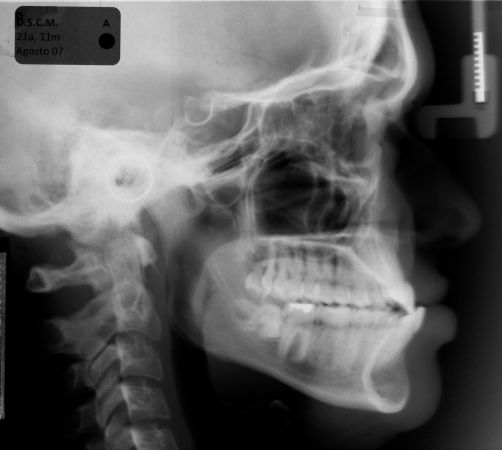

Tratamento da maloclusão de Classe III com elásticos intermaxilares e controle mecânico do arco inferior